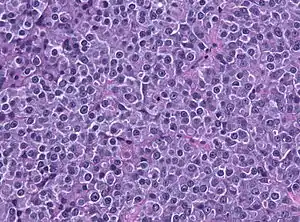

Invasive prolactinoma showing invasion into the left temporal lobe